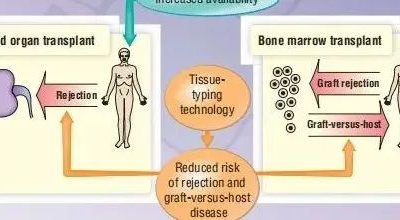

导 读

上图说明了本章的主题,它描述了抗体如何与几乎有无限种形状的抗原相互作用,以及这种相互作用如何保护我们免受病原体的侵袭。本章还回顾了抗原或抗体存在的非常特异的诊断试验的发展。抗体-抗原相互作用的最显著的特征是它们的特异性和亲和力。除此之外,抗体-抗原的相互作用很像其他受体-配体的相互作用。抗体与抗原之间的相互作用涉及物理化学力,类似于酶与其底物(或竞争性抑制剂)之间的相互作用,或受体(如胰岛素受体)与配体(如胰岛素)之间的相互作用。这些力来源于四个方面:(1)带电侧链之间的静电相互作用,(2)氢键,(3)范德华力,(4)疏水相互作用。